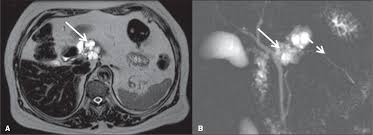

Resumo: A Síndrome de Von Hippel–Lindau (VHL) é uma facomatose com predisposição a hemangioblastomas, carcinoma de células renais, tumores pancreáticos e feocromocitomas. A investigação por imagem deve ser ampla e sensível, priorizando RM com contraste para SNC e coluna e exame abdominal com contraste para caracterização de lesões renais e pancreáticas.

- Objetivo: identificação de carcinoma de células renais, cistos pancreáticos e tumores neuroendócrinos.

- Abdômen (rins e pâncreas): RM com e sem contraste anual, exames alternando com ultrassom :contentReference[oaicite:3]{index=3}.